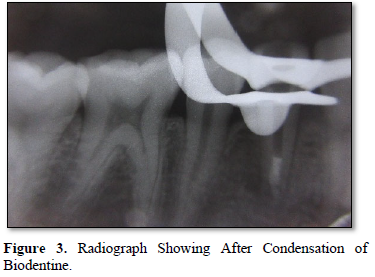

After administering local anesthesia, rubber isolation was made. The access cavity was prepared with the help of Endo access and Endo Z bur. After creating straight line access, the working length was measured with the help of conventional radiograph by using 80 no k file. After confirming the working length, cleaning and shaping of the cavity was done by 80 no k file in a circumferential manner. The canal was irrigated with 2.5 % NAOCL and final irrigation was done with normal saline. Then calcium hydroxide medicament dressing was done. After 2 weeks patient was recalled and cavity is irrigated with NAOCL and normal saline. The canals were dried with paper points. After drying the canal Biodentine was mixed according to the manufacturer’s instructions and condensed into the canal carefully with the help of plugger until it creates 5 mm of apical plug. The remaining canal space is obturated with gutta-percha. Finally, the cavity is restored with composite restoration (Figures 1-5).